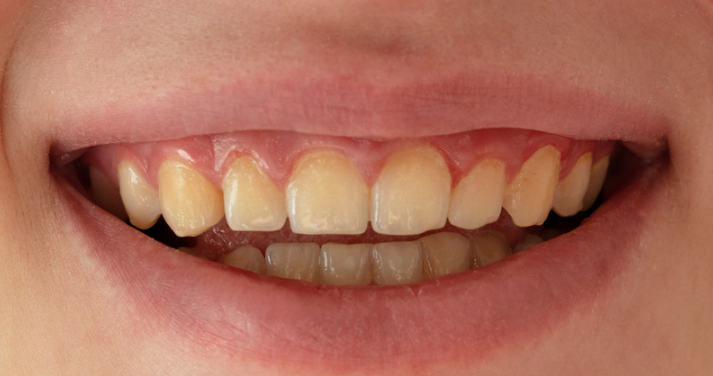

6.1 Gingivitis

Prevalence

Gingivitis is relatively common in children. It occurs in about half the population by four or five years of age and increases with age.

Signs and symptoms

Inflamed red gums, bleeding on touching or when soft brushing occurs, oedema (swollen gums).

Causes

Gingivitis is caused by the accumulation of plaque on the teeth and in the crevice between the gums and the teeth. Important contributors are crowded teeth and mouth breathing, which dries the gingiva